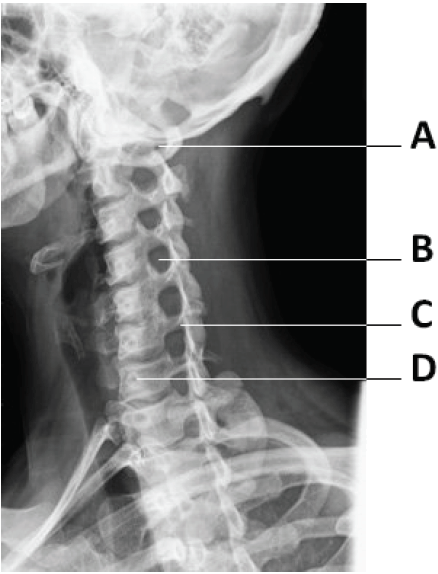

I. A figura representa o posicionamento oblíquo da coluna e demonstra os forames intervertebrais.

II. A figura mostra uma imagem radiográfica AP da coluna cervical.

III. A figura representa um perfil da coluna com a apresentação das sete vértebras cervicais.

IV. Na figura, A representa o arco posterior e o tubérculo de C1 e em B, o forame intervertebral entre C4 e C5.